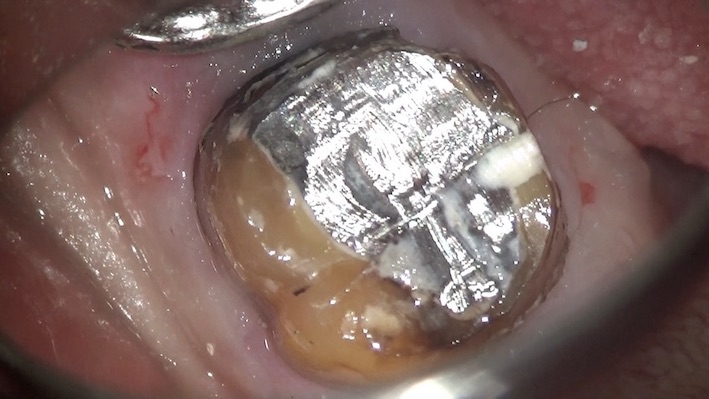

ある患者さんがメインテナンスにいらっしゃしました。衛生士が詳しく見てみると・・・

被せ物の下から虫歯になっていることがわかりました。

すぐに被せ物を外し、内部を見てみると、

金属の土台が装着されていました。